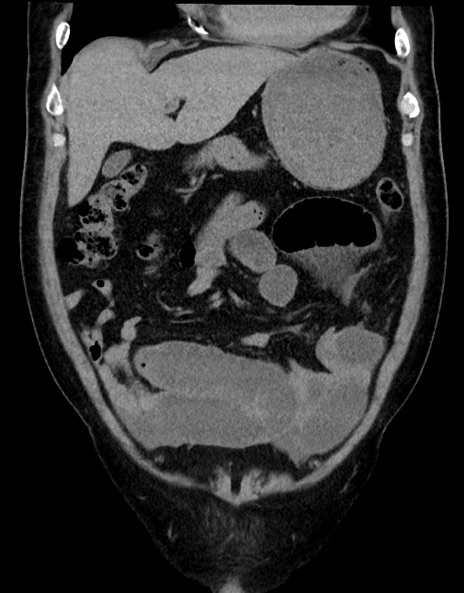

横断像

【症例】70歳代男性

【主訴】腹痛

【現病歴】今朝から腹痛あり。全体的に痛い。特に左上の方。排ガスが今日はない。冷や汗が出る。

【既往歴】直腸癌術後

【身体所見】左側腹部〜上腹部に圧痛あり。腹膜刺激症状明らかなではない。軽度反跳痛。左下腹部に術後瘢痕あり。

【データ】WBC 7700、CRP 0.02